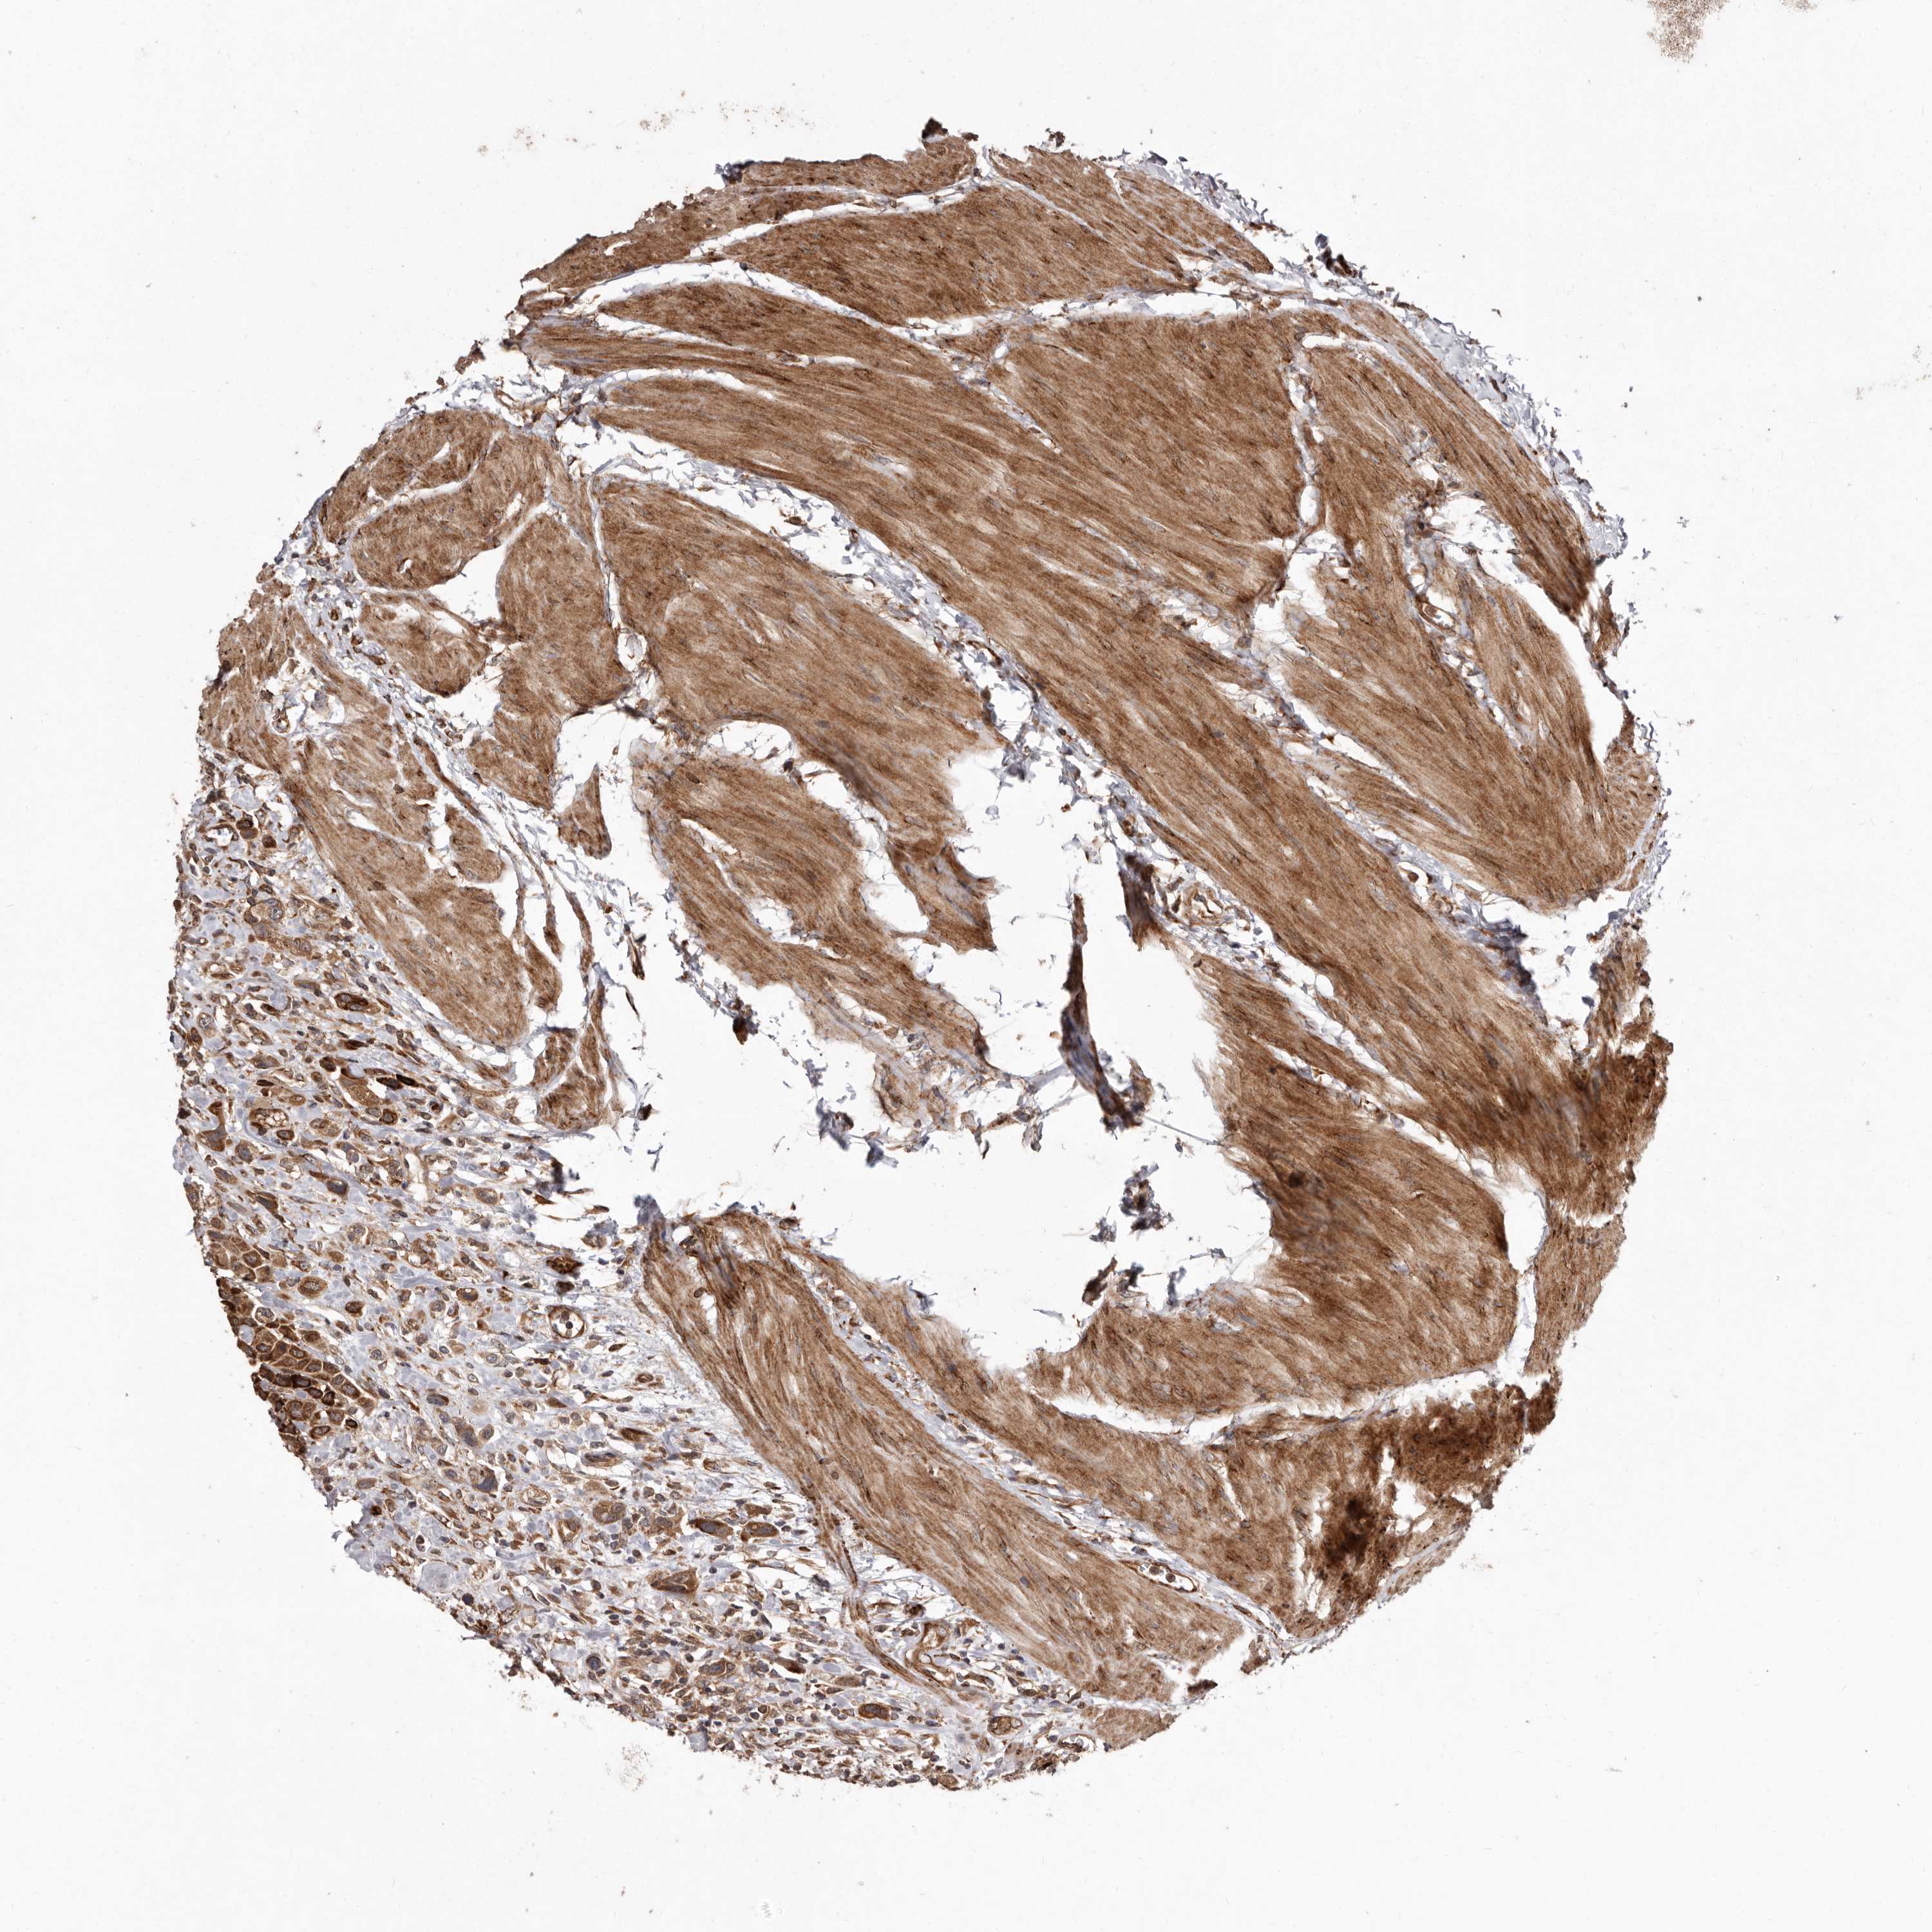

UROTHELIAL CANCER - Protein expressioni

A mouse-over function shows sample information and annotation data. Click on an image to view it in a full screen mode. Samples can be filtered based on level of antibody staining by selecting one or several of the following categories: high, medium, low and not detected. The assay and annotation is described here.

Note that samples used for immunohistochemistry by the Human Protein Atlas do not correspond to samples in the TCGA dataset.

Antibody stainingi

Antibody staining in the annotated cell types in the current human tissue is reported as not detected, low, medium, or high, based on conventional immunohistochemistry profiling in selected tissues. This score is based on the combination of the staining intensity and fraction of stained cells.

Each image is clickable and will lead to virtual microscopy that enables deeper exploration of all samples and also displays staining intensity scores, fraction scores and subcellular localization as well as patient and tissue information for each sample.

Antibody HPA028476

Antibody HPA028486

Antibody HPA028563

Staining

High

Medium

Low

Not detected

Intensity

Strong

Moderate

Weak

Negative

Quantity

>75%

75%-25%

<25%

None

Location

Nuclear

Cytoplasmic/membranous

Cytoplasmic/membranous,nuclear

Urothelial carcinoma, Low grade

Urothelial carcinoma, High grade